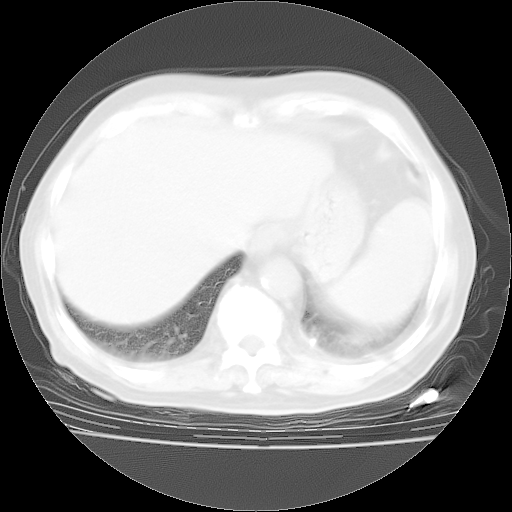

4月28日肺部CT——再次出现类似去年5月9日——透光度降低,“间质性”改变。

4月28日肺部CT——再次出现类似去年5月9日——磨玻璃样、间有“粟粒样”改变。